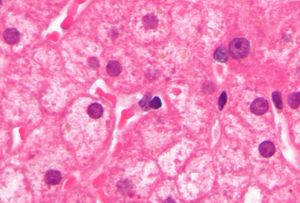

وفي الآونة الأخيرة، قد تم تطوير اختبارات PCR للكشف وقياس كمية الحمض النووي الڤيروسي في العينات الطبية. وتسمى هذه الاختبارات الحمل الڤيروسي وتستخدم لتقييم حالة عدوى الشخص ولرصد علاج.[25] ويوجد في الأفراد مع الحمل الڤيروسي العالى، خلايا كبدية كالزجاج المجروش مميزة في العينات الحية.

أما العدوى المزمنة لڤيروس التهاب الكبد البائي قد تكون بلا أعراض أو قد تترافق مع التهاب مزمن في الكبد (التهاب الكبد المزمن)، مما يؤدي إلى تليف الكبد على مدى عدة سنوات. هذا النوع من العدوى يزيد بشكل كبير من حالات سرطان خلايا الكبد. ولذلك يتم تشجيع المزمن حامل العدوى على تجنب تناول الكحول نظرا لأنه يزيد من مخاطر التعرض لتليف الكبد وسرطان الكبد. وقد ارتبط ڤيروس التهاب الكبد باء بحدوث التهاب الكلية الغشائي (MGN).[8]

يكون الأشخاص المصابون بإنتان مزمن لاعرضيين عادة، وقد لا يكونون مدركين لإصابته بالإنتان، رغم أنهم قادرون على نقل العدوى لغيرهم. إن الإنتان المزمن هو المسؤول عن أغلب حالات المراضة morbidity والوفيات المتعلقة بڤيروس HBV، ويشمل ذلك التهاب الكبد المزمن والتشمع والفشل الكبدي وسرطانة الخلية الكبدية. يتطور التهاب الكبد المزمن الفعال عند أكثر من 25٪ من الحملة، وغالباً ما يؤدي للتشمع. ويقدر في الولايات المتحدة أن ما بين 3000 و4000 شخص يموتون سنوياً بسبب التشمع الناجم عن التهاب الكبد B. يزداد خطر سرطانة الكبد عند الأشخاص المصابين بإنتان مزمن بڤيروس HBV إلى 12 - 300 ضعف مقارنة مع غير الحملة. ويقدر وفاة 1000 - 1500 شخص سنوياً في الولايات المتحدة بسبب سرطان الكبد الناجم عن التهاب الكبد B.

وتوجد عدوى ڤيروس التهاب الكبد ب المزمنة في 0.5٪ من البالغين في أمريكا الشمالية، وفي 0.1٪ إلى 20٪ في أجزاء أخرى من العالم. وبعد العدوى الحادة بڤيروس التهاب الكبدي ب، يختلف خطر تطور العدوى إلي مزمنة عكسياً مع السن؛ وتحدث العدوى المزمنة بڤيروس الالتهاب الكبدي ب في حوالي 90٪ من الرضع الذين يصابون بالعدوى عند الولادة، و20٪-50٪ من الأطفال الذين يصابون بالعدوى بين سن 1-5 سنوات، و1٪-10٪ في الأشخاص المصابين بالعدوى كأطفال أكبر من ذلك والبالغين. وعدوى ڤيروس الالتهاب الكبدي ب المزمنة شائعة في الأشخاص الذين لديهم عوز مناعي. وقد يكون أو لا يكون لدى المصابين بالعدوى المزمنة سوابق التهاب كبد سريري. ويشاهد في حوالي الثلث ارتفاع في ناقلات الأمين؛ وتتراوح نتائج الخزعة من "خزعة سوية" إلى التهاب كبدي نخري وخيم مع أو دون تشمع. ويقدر أن 15٪-25٪ من الأشخاص المصابين بعدوى ڤيروس التهاب الكبد (ب) المزمن سوف يموتون موتاً مبكراً إما بسبب التشمع أو بسبب السرطانة الخلوية الكبدية. وڤيروس التهاب الكبد ب هو السبب في حوالي 80٪ من مجموع حالات السرطانة الخلوية الكبدية على نطاق العالم.